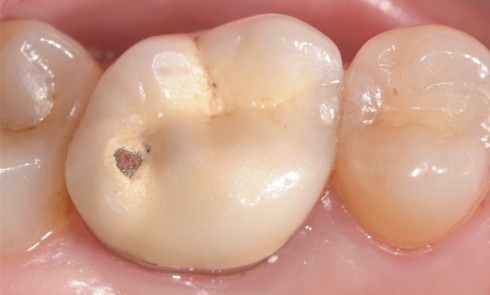

Présentation du cas Il s’agit d’un patient adulte de 28 ans (fig. 1) présentant une classe I, une dysharmonie dento-maxillaire (DDM),...